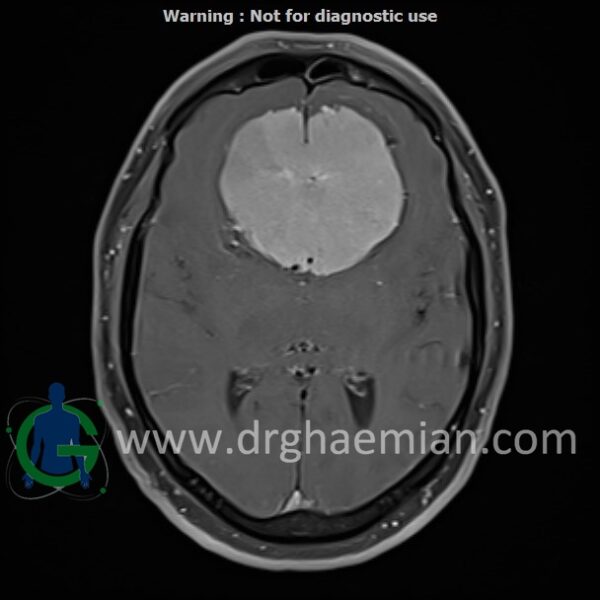

ام آر آی هیدروسفالی غیر ارتباطی

ام آر آی هیدروسفالی غیر ارتباطی بیمار

ام آر آی مغز یک روش تصویربرداری است که با استفاده از آهنرباهای قوی و امواج رادیویی تصاویری از مغز و بافت های عصبی پیرامونی آن ایجاد می کند. در …